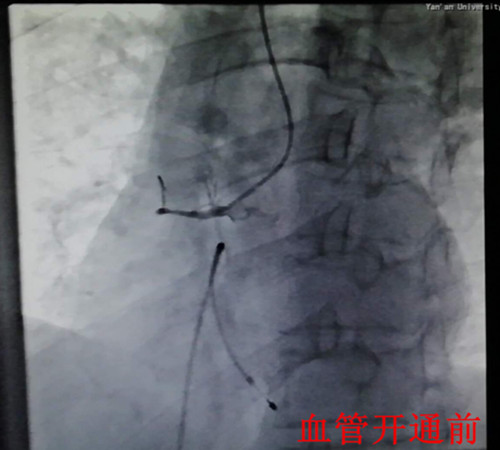

在一陣有效地搶救之后,患者在氣管插管、呼吸機輔助呼吸下,先行心臟臨時起搏器置入,后行左右冠狀動脈造影,造影顯示:右冠狀動脈呈鼠尾狀,開口5mm處100%閉塞,旋支血管中遠段60—99%彌漫狹窄病變。手術(shù)者立即開通右冠狀動脈,盡管患者在手術(shù)過程中不斷出現(xiàn)室速室顫,血壓下降,但隨著右冠狀動脈遠端血流恢復(fù),患者終于生命體征趨于平穩(wěn),安全返回監(jiān)護室繼續(xù)下一步治療。